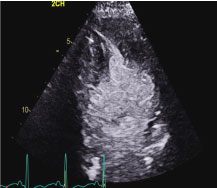

ECG revealed sinus rhythm and non-specific ST changes (Figure 3). The echocardiogram revealed an akinetic apex and dynamic basal function (Figure 4 and Movie 2).

Figure 4: Apical 2 chamber end-systolic still frame revealing apical akinesia and basal contraction. View Figure 4

Movie 2: Echocardiographic Apical 2 chamber view of the left ventricle with contrast revealing left ventricular apical dyssynergy (red arrow) and left ventricular basal hyperkinesia (yellow arrow). The echocardiographic features represent the subtype of stress-induced cardiomyopathy called apical Takotsubo cardiomyopathy.